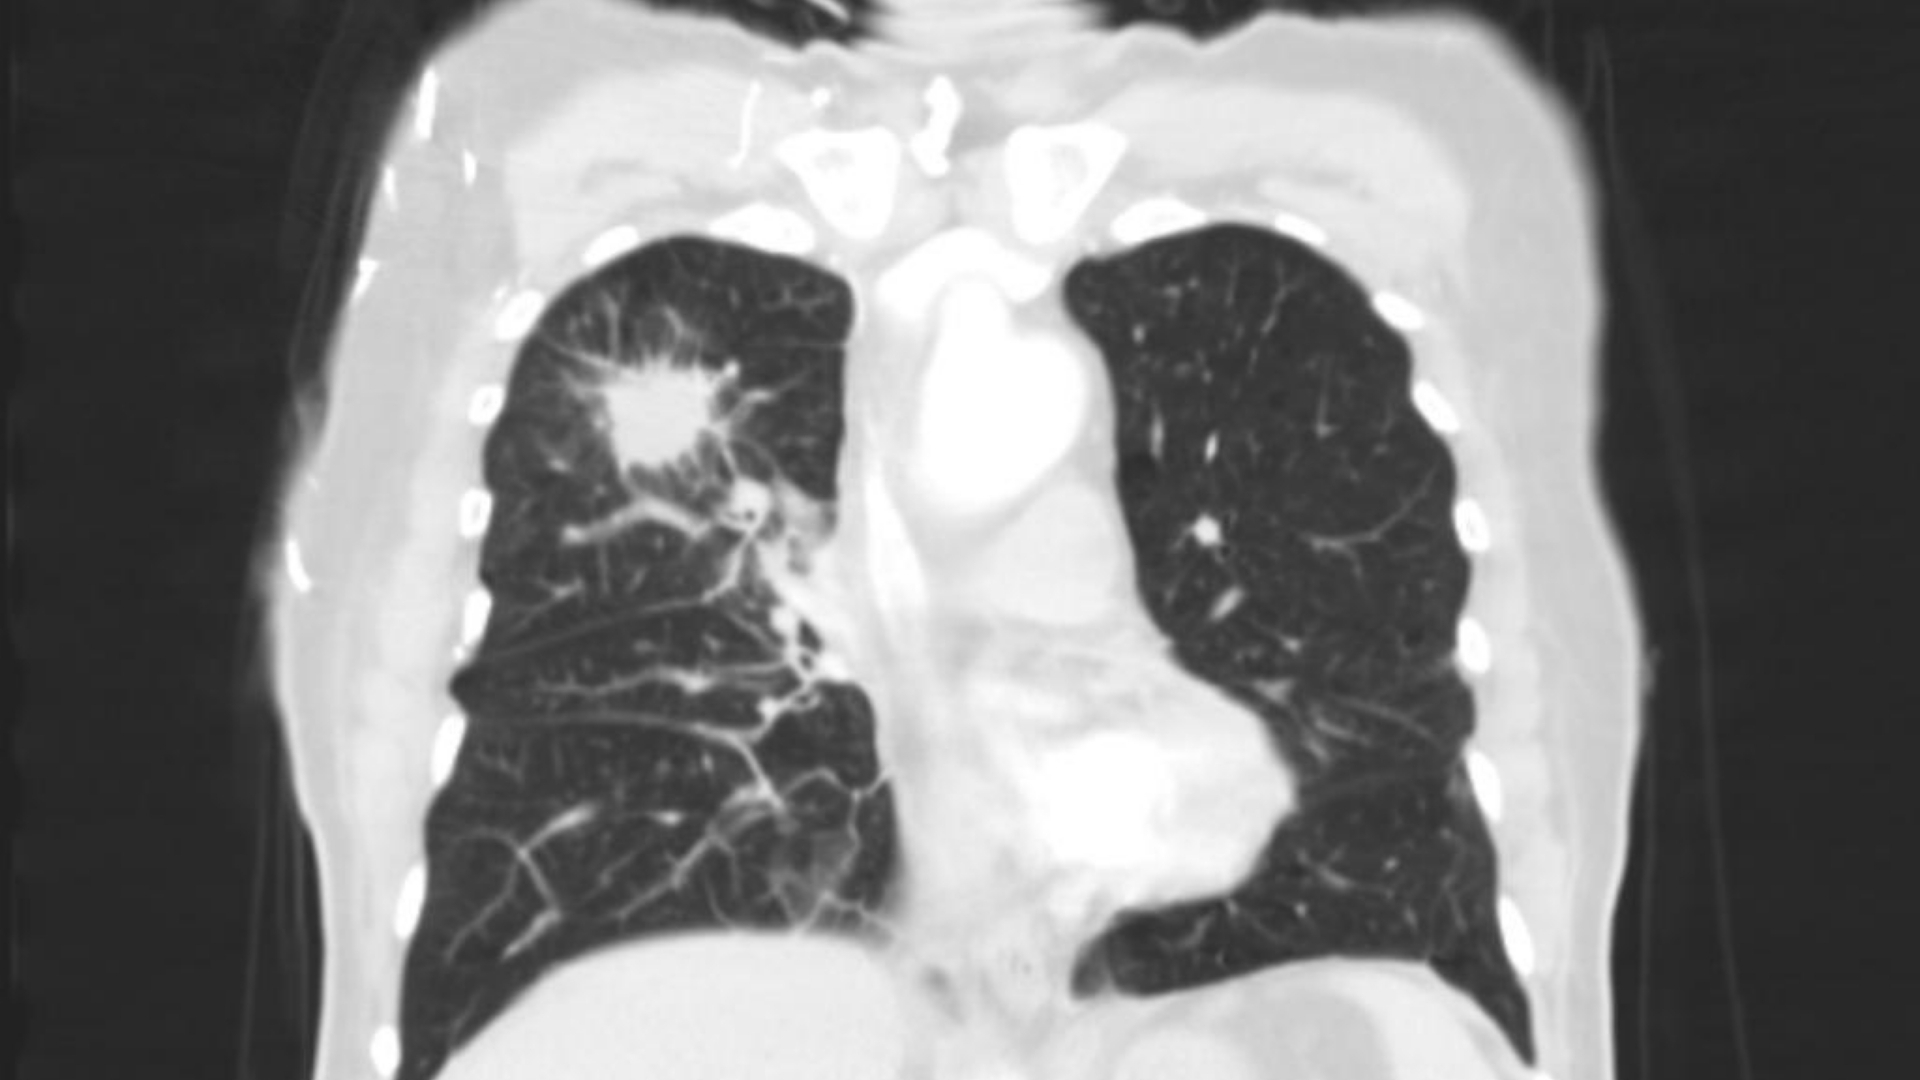

肺癌

在傳統化療和放射治療失敗後,4D 治療的機器人微波消融術 精確度 針對我的肺部轉移腫瘤,零併發症。結合新陳代謝重整 禁食 + 補充酮 和定時免疫治療 節奏我的腫瘤在三個月內縮減了 70%。我現在已是 NED(無病徵),可以繼續遠足大嶼山!"

結腸癌肺轉移